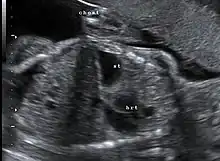

Congenital diaphragmatic hernia (CDH) is a birth defect of the diaphragm. The most common type of CDH is a Bochdalek hernia; other types include Morgagni hernia, diaphragm eventration and central tendon defects of the diaphragm. Malformation of the diaphragm allows the abdominal organs to push into the chest cavity, hindering proper lung formation.

This condition can often be diagnosed before birth and fetal intervention can sometimes help, depending on the severity of the condition.[8] Infants born with diaphragmatic hernia experience respiratory failure due to both pulmonary hypertension and pulmonary hypoplasia. The first condition is a restriction of blood flow through the lungs thought to be caused by defects in the lung. Pulmonary hypoplasia or decreased lung volume is directly related to the abdominal organs presence in the chest cavity which causes the lungs to be severely undersized, especially on the side of the hernia.